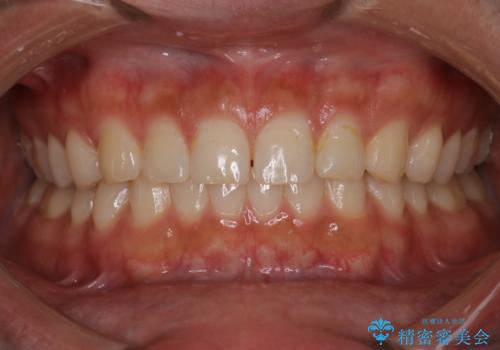

マウスピースの使用時間が短いため、シュミレーション通り進むか不安でしたが

治療期間1年で、主訴である前歯のがたつきを改善出来、

奥歯の噛み合わせも良くなりました。